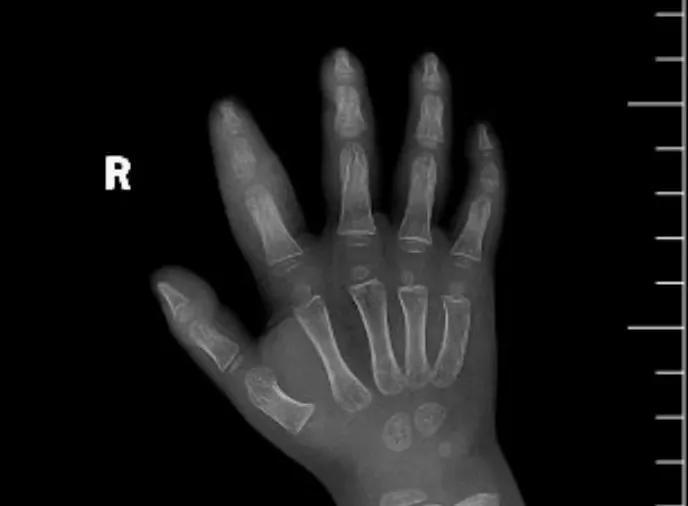

近日,市二院顯微外科接診一名3歲半的小患者,被玉米葉割傷右食指,因家長疏忽大意,導(dǎo)致一個小小的傷口竟然發(fā)展成了骨髓炎。來院時患兒右食指腫脹明顯,既不能伸也不能彎,皮膚發(fā)燙,疼得哇哇大哭。

第三天開始,月月哭鬧不止,一直說手疼,怎么哄也不行,于是在當(dāng)?shù)蒯t(yī)院治療了10來天,然而月月的手指依然腫得像個胡蘿卜,疼痛感依然存在。此時,月月的媽媽才覺得事情不大對勁,于是經(jīng)過打聽,慕名來到市二院顯微外科。入院后,經(jīng)檢查發(fā)現(xiàn),月月的右食指骨質(zhì)有侵蝕,骨骺有缺損,甚至?xí)绊懸院笫种傅陌l(fā)育。聽到這個消息,月月媽媽感覺心都揪住了。

隨后,經(jīng)顯微外科團(tuán)隊(duì)充分的討論,制定了科學(xué)細(xì)致的治療方案,為月月做了感染灶清除及手指的開放引流,并留取了標(biāo)本做細(xì)菌培養(yǎng),為進(jìn)一步的合理用藥提供依據(jù)。經(jīng)過兩周的治療,月月的手指終于順利消腫愈合,并且手指功能活動良好。說起這一個多月的煎熬,月月媽媽不禁落淚,但總算是治愈了,笑容又重新回到她們一家的臉上。